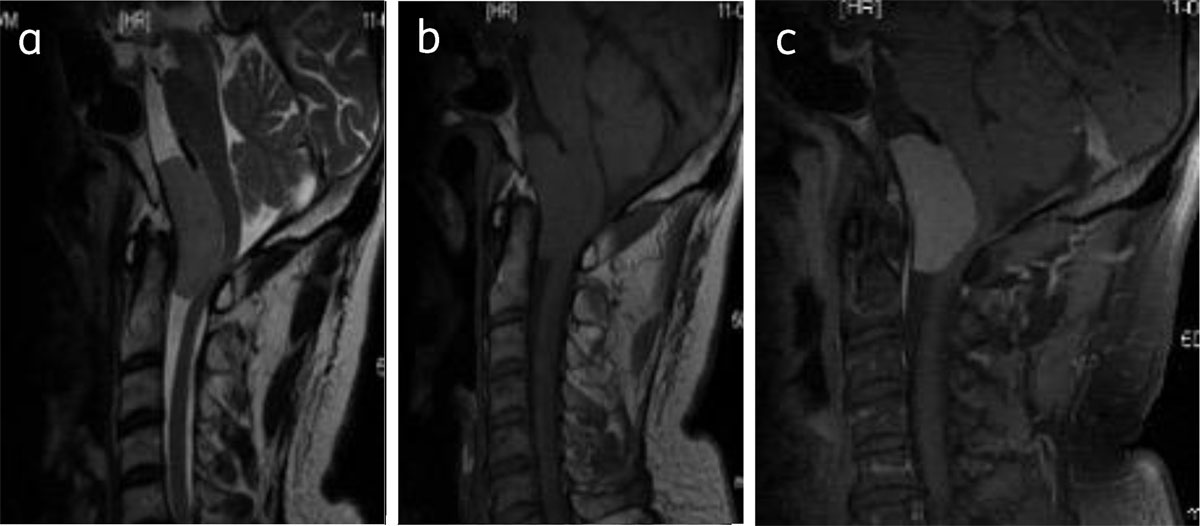

Figure 8

Clival meningioma: Sagittal T2WI (a), T1WI (b), and post contrast T1W (c) shows foramen magnum meningioma (asterisk) causing compressive myelopathy.